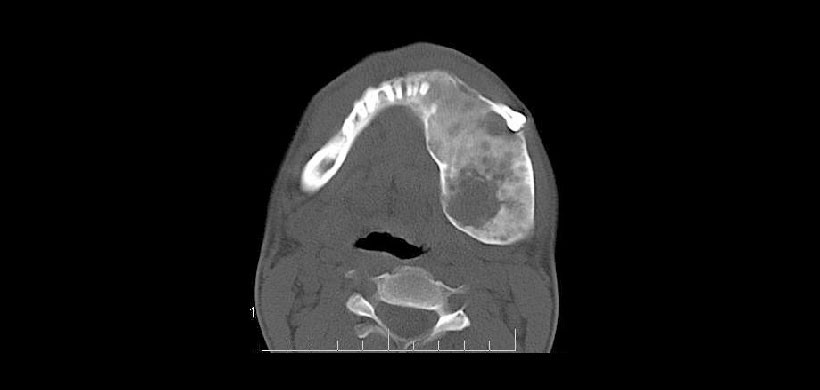

Figura 3: Corte axial de TC con ventana ósea que revela la participación de los huesos temporales, cigomáticos, frontales y etmoidales. El hueso esfenoidal también se ve comprometido e involucrado en el estrechamiento del canal óptico y en las fisuras orbitarias.